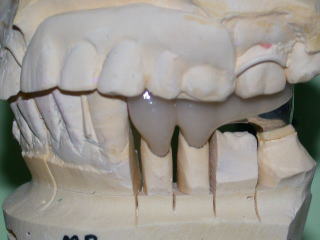

上下の補綴スペース(上部構造物:セラミックスや金属の冠の入る隙間)を確認します。

平成20年3月、上部構造物4本を装着しました。

頬側面観です。

構造は白金加金製の金属フレームに、セラミックスを焼き付けてあります。

金属だけよりも審美性に優れ、セラミックスだけよりも耐久性は向上しますが、製作手順が複雑です。

歯科技工士の熟練した技術が必要となり、金額も高めです。